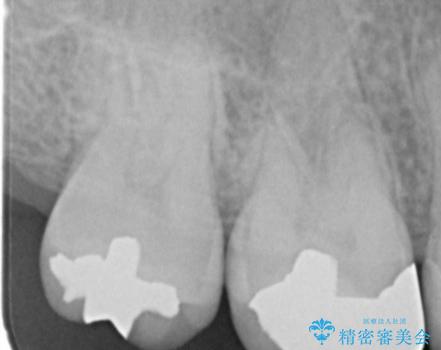

縁下歯石のクリーニングの症例写真

縁下歯石のクリーニング

1. 縁下歯石のクリーニングの治療前